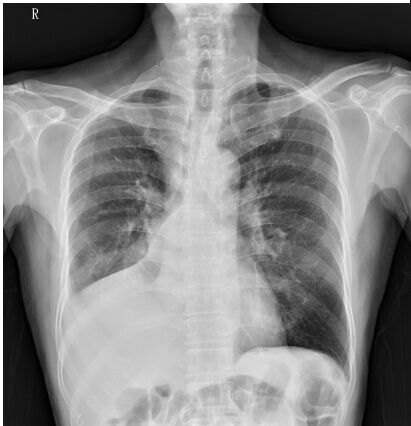

8. 63歲男性,因為鬱血性心臟衰竭住院,BMI 42 kg/m², 入院時氧氣濃度(SaO2)為75% , 血壓為140/80 mmHg。胸部X光顯示肺水腫,心跳數為136/min,同時合併出現非持續性心室頻脈(non-sustained ventricular tachycardia)。心臟超音波顯示兩心室(左右心室)功能皆不全,左心室射出分率為15%, 實驗室檢查顯示,腎功能: creatinine clearance 80 ml/min, NTproBNP 3000 pg/ml, 右心導管顯示低心輸出率 (cardiac index of 1.5 l/min/m²),肺動脈楔壓(PCWP)為20 mmHg。下列心衰竭藥物的注射選擇何者最為恰當? (A) Dobutamine 1~2 ug/kg/min 靜脈注射。 (B) Dopamine 10 ug/kg/min 靜脈注射。 (C) Norepinephrine 3ug/kg/min 靜脈注射。 (D) Levosimendan 0.10 ug/kg/min 靜脈注射。 (E) Dopamine 2 ug/kg/min 靜脈注射。